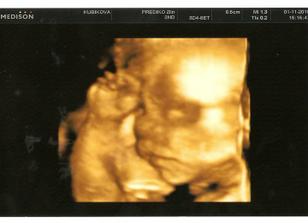

1.11. 3D ultrazvuk 🙂